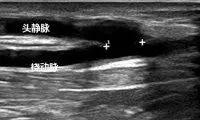

目前维持性血液透析患者多为高龄、合并糖尿病、肥胖、血管条件欠佳,易形成血栓、非血栓性狭窄或动脉瘤等并发症,并发症的及时诊治尤其重要。北京清华长庚医院肾内科联合血管外科、超声科和放射科建立了血液透析通路合作组,将急诊超声、CT动静脉血管造影、药物溶栓、血管介入及外科手术等进行整合,为紧急通路溶栓及血管通路建立困难的患者提供全方位诊治,使患者获益。

3.20日晚举行了多学科联合讨论会,肾内科李敏侠医师首先介绍了透析通路的最新进展、维护及监测方法,血管外科赵俊来医师结合病例对通路血栓、内瘘狭窄、介入及手术最新治疗进展进行了系统讲解,超声科白志勇副主任医师对通路血栓及狭窄的超声检查方法进行了详细的阐述,透析室武向兰护士长从护理角度阐明人工血管通路并发症的防范方法。肾内科李月红主任、血管外科吴巍巍主任、超声科张华斌主任、放射科郑卓肇部长对急诊超声、急诊溶栓、透析通路CT动静脉造影、超声下球囊扩张、PTA、支架及人工血管手术等进行了讨论并达成共识。